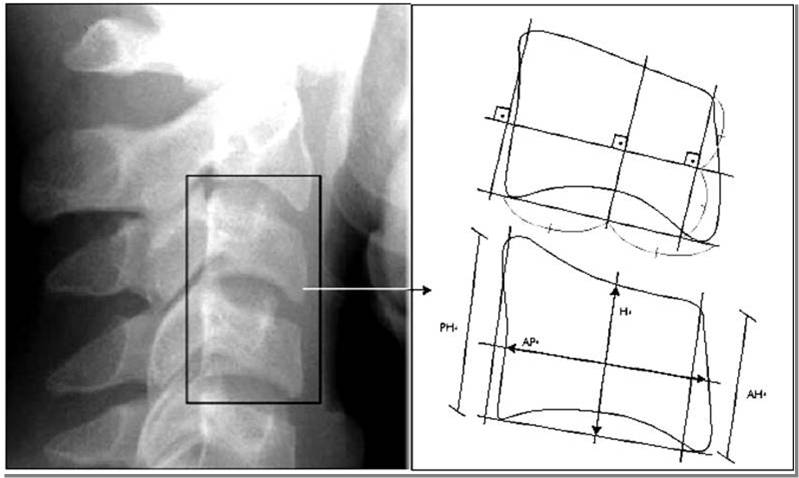

This study evaluated the applicability of the method developed by Caldas to measure vertebral bone age for Brazilians suffering from Down syndrome. A database comprised of 57 case records of individuals with this syndrome, both male and female, with age ranging between 5 and 18 years, was assessed. These records had lateral cefalometric radiographies and radiographies of hand and wrist, being all obtained on the same date. Also, 48 records of individuals not suffering from Down syndrome were assessed. For the hand and wrist radiographies the Tanner and Whitehouse (TW3) method was used, and bone age was obtained. The Caldas method was employed on the lateral cefalometric radiographies in order to obtain the vertebral bone age. From the information about the bone age, vertebral bone age and chronological age, the Wilcoxon test was used to compare all the ages in pairs. There was a statistically significant difference between the three ages mentioned above for both male and female control group and female Down syndrome group. Therefore, this method was only suitable for  Down syndrome male individuals. Based on the results, a formula to obtain the bone age for Down syndrome individuals was developed.